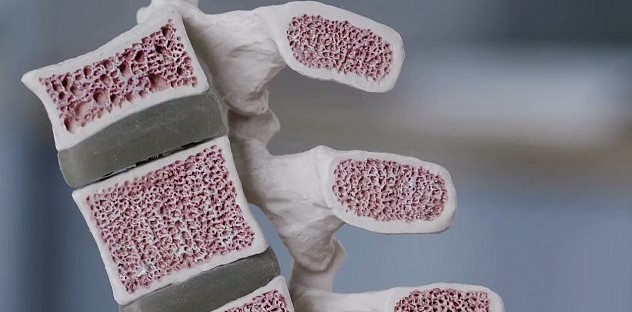

Structure of Microlattice is highly influenced by human bones, which possess a rigid structure from outside but consist of hollow tubes from the inside which bring lightness on par with the strength. This kind of structure also provides the ability to absorb a whole lot of energy, as an egg wrapped in Microlattice would survive a drop from a 25 story building. They completely recover their shape after significant compression.